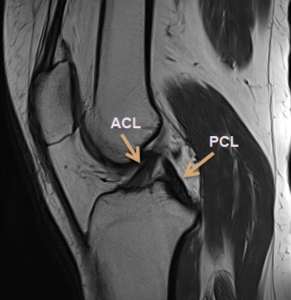

Diagnosis

MRI scan

Anatomic placement of an anterior cruciate ligament (ACL) graft is critical

to the success and clinical outcome of ACL reconstruction. Anatomic ACL graft placement is defined as positioning the ACL femoral and tibial bone tunnels at the center of the native ACL femoral and tibial attachment sites.